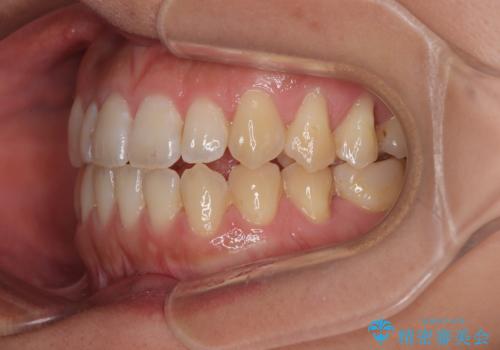

- 極端な開咬を気にして来院された患者様です。

開咬の方の特徴として、幼少期の指しゃぶりの癖や、強い舌の突出癖が挙げられます。

こちらの患者様も強い舌の突出癖が認められたため、矯正治療を行うにあたり、舌のトレーニングをしっかりと行っていただくように指示をいたしました。

開咬はインビザラインが得意とする歯列不正であるため、舌のトレーニングを行いながら、インビザラインにて矯正治療を行うこととしました。

担当医としては、もっと上下の前歯を接触させるところまで治療を進めたいという思いがありますが、今まで咀嚼できなかったものが食べられるようになったということで、この状態で治療終了となりました。